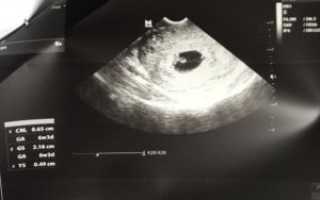

На ранних сроках беременности ультразвуковое исследование (УЗИ) важно для оценки состояния плода и выявления аномалий. Однако иногда близнецы не обнаруживаются на УЗИ, что может вызвать беспокойство у родителей. В статье рассмотрим причины, по которым близнецы могут не быть видны на УЗИ на сроке 7 недель, а также важность тщательной диагностики и мониторинга беременности. Эта информация поможет родителям лучше понять процесс и нюансы ранней диагностики.

Можно ли на УЗИ в 7 недель беременности не увидеть двойню?

В 7 недель беременности на УЗИ двойня определяется достоверно.